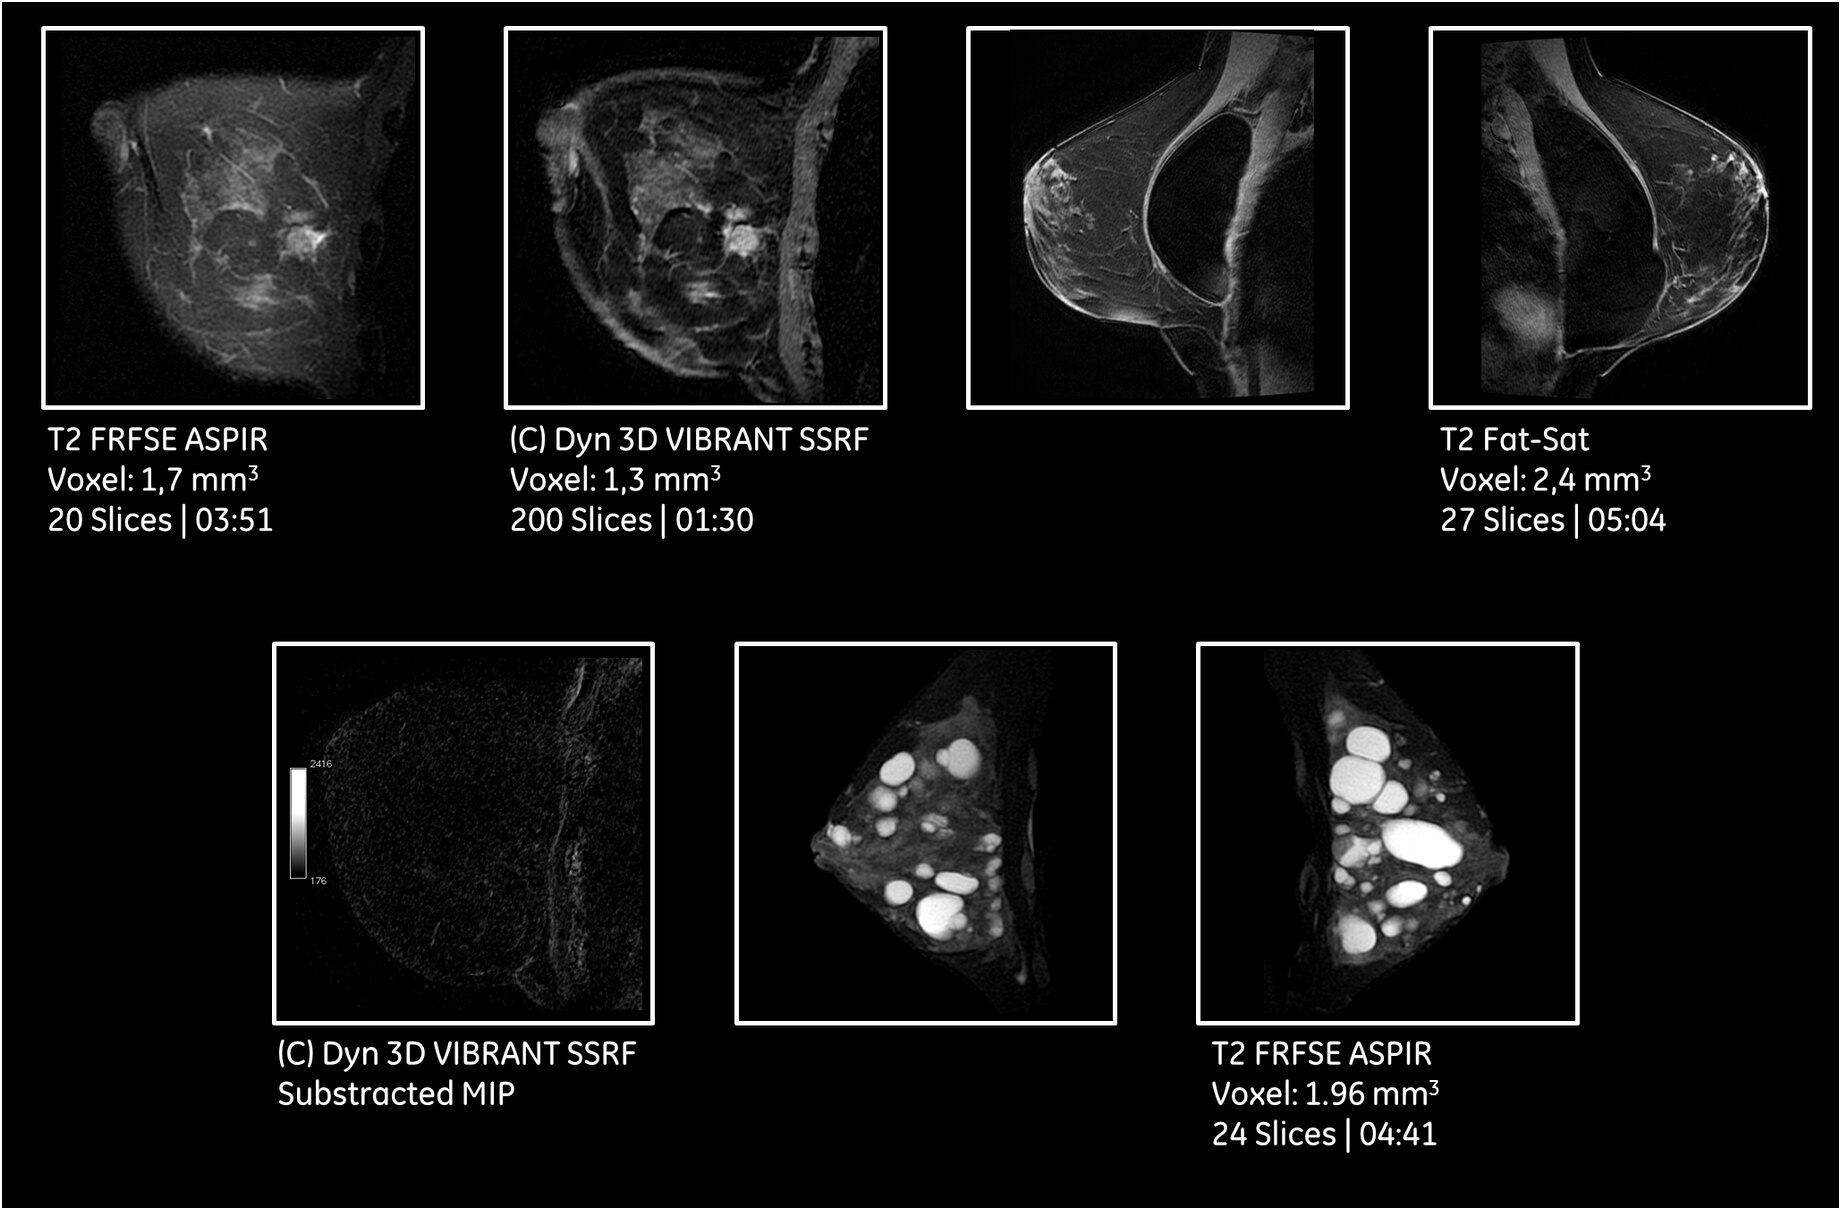

Breathe Free

With its free-breathing imaging applications and advanced motion correction software, SIGNA Pioneer will compensate for patient movement and allow complete free-breathing body imaging. This includes dynamic contrast enhanced MR imaging, improving dramatically

patient experience but also image quality in very challenging situations.